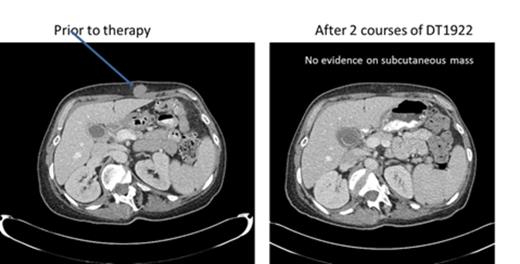

We conducted a phase 1 study to assess safety, to determine the maximum tolerated dose (MTD) and to evaluate preliminary efficacy in patients with chemotherapy refractory B cell leukemia or lymphoma expressing CD19 and/or CD22. DT2219 was administered in a single course intravenously over 4 hours (1-2 hours for subsequent doses) every other day for 4 total doses. The starting dose was 0.5 µg/kg/dose (2.0 ug/kg/course) (1/1000th of the MTD in rabbits). The dose was escalated by accelerated design until dose limited toxicity (DLT) was observed. Twenty-two patients were enrolled, with a median age of 55 years (range, 34-78). Five patients had pre-B acute lymphoblastic leukemia (4 refractory, 1 with extra-medullary disease, 1 had chronic lymphocytic leukemia (CLL) and 7 had non-Hodgkin lymphoma). All were chemo-refractory with a median of 4 prior therapies. All patients had biopsy-confirmed tumor expression of CD19 and/or CD22. The first 9 patients were treated at doses ranging from 0.5 ug/kg/dose to 20 ug/kg/dose. No drug was detectable in those patients and they experienced no DLT or clinical responses. DT2219 was detectable in the serum at doses ≥40 µg/kg/dose (N=13). Dose levels were 40 µg/kg/day N=5; 60 µg/kg/day N=5; 80 µg/kg/day N=3. The area under the curve (AUC ) range was 1,104 -1,346 and the half-life ranged from 54-84 minutes. After a single course of DT2219 we observed partial remission in a 77 year old patient with rituximab/chemotherapy-refractory CLL (dose level 40 µg/kg). The 40% reduction in the abdominal tumor mass is shown in Figure 1. This patient did not experience any DLT. A second partial remission was observed in 53 year old patient with relapsed marginal zone lymphoma (dose level 60 µg/kg) who experienced a DLT of capillary leak syndrome. After regulatory approval, that patient received a second treatment course 8 weeks later at a reduced dose of 40 µg/kg which resulted in a complete remission (Figure 2). Both patients are alive and in remission at 6 and 4 months, respectively, after therapy. Adverse events were observed in all patients who received ≥40 µg/kg. The most common was grade 1-2 capillary leak syndrome, grade 1-2 hematologic toxicity, elevated liver function tests and fatigue. Two patients experienced DLTs: at the 40 µg/kg dose (grade 3 lower extremity weakness) and 60 µg/kg dose ( grade 4 neutropenia and grade 3 capillary leak). All adverse reactions resolved completely within one week. Immunogenicity and formation of neutralizing antibodies is a major barrier in development of DT-based immunotoxins. Remarkably, none of the 8 patients with B-cell lymphoma/CLL who had received rituximab within weeks preceding therapy with DT2219 had detectable neutralizing antibody. These patients had no detectable B cells at the time of study drug administration. This suggests that rituximab pre-treatment may prevent the development of neutralizing antibodies and allow for repetitive dosing. In conclusion, we have demonstrated promising clinical efficacy of the novel immunotoxin DT2219 in refractory B cell lymphoid malignancies. We determined that the biologically active dose of DT2219 is between 40-80 µg/kg and that repetitive dosing is feasible in patients pre-treated with rituximab. Phase 2 trial is in development.

53 year old female with CD22+CD19+ relapse marginal zone lymphoma received 2 courses of DT1922 ( 60 µg/kg and 40 µg/kg) and attained a complete resolution of subcutaneous tumor mass.